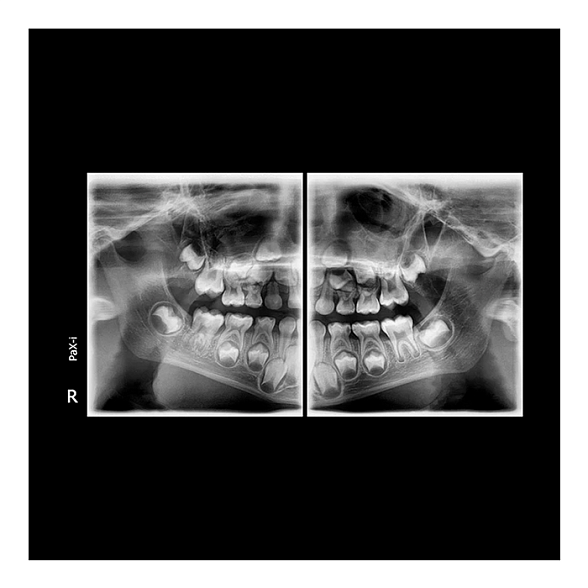

Цифровой дентальный томограф X-Radius Compact 3D — это современное решение для стоматологических клиник, стремящихся к повышению качества диагностики при разумных инвестициях. Аппарат сочетает в себе передовые технологии получения трехмерных изображений, надежность и эргономичный дизайн, что делает его идеальным выбором для широкого спектра задач: от имплантологии и эндодонтии до ортодонтии и хирургии.

Ключевой особенностью X-Radius Compact 3D является компактный размер FOV (поля обзора) 10х10 см. Этот формат оптимален для получения детализированных снимков одной или двух челюстей, области гайморовых пазух, височно-нижнечелюстных суставов. Он позволяет минимизировать дозу облучения для пациента, обеспечивая при этом всю необходимую информацию для планирования лечения.

- Высокое качество изображений: Цифровой плоскопанельный детектор обеспечивает высокое разрешение и контрастность снимков, что критически важно для оценки анатомических структур, состояния корневых каналов, положения зачатков зубов.

- Хирургическая стоматология: Диагностика ретинированных и дистопированных зубов, оценка состояния периапикальных тканей, планирование операций.

- Ортодонтия: Анализ положения зубов, оценка состояния корней, планирование лечения на брекет-системах или элайнерах.